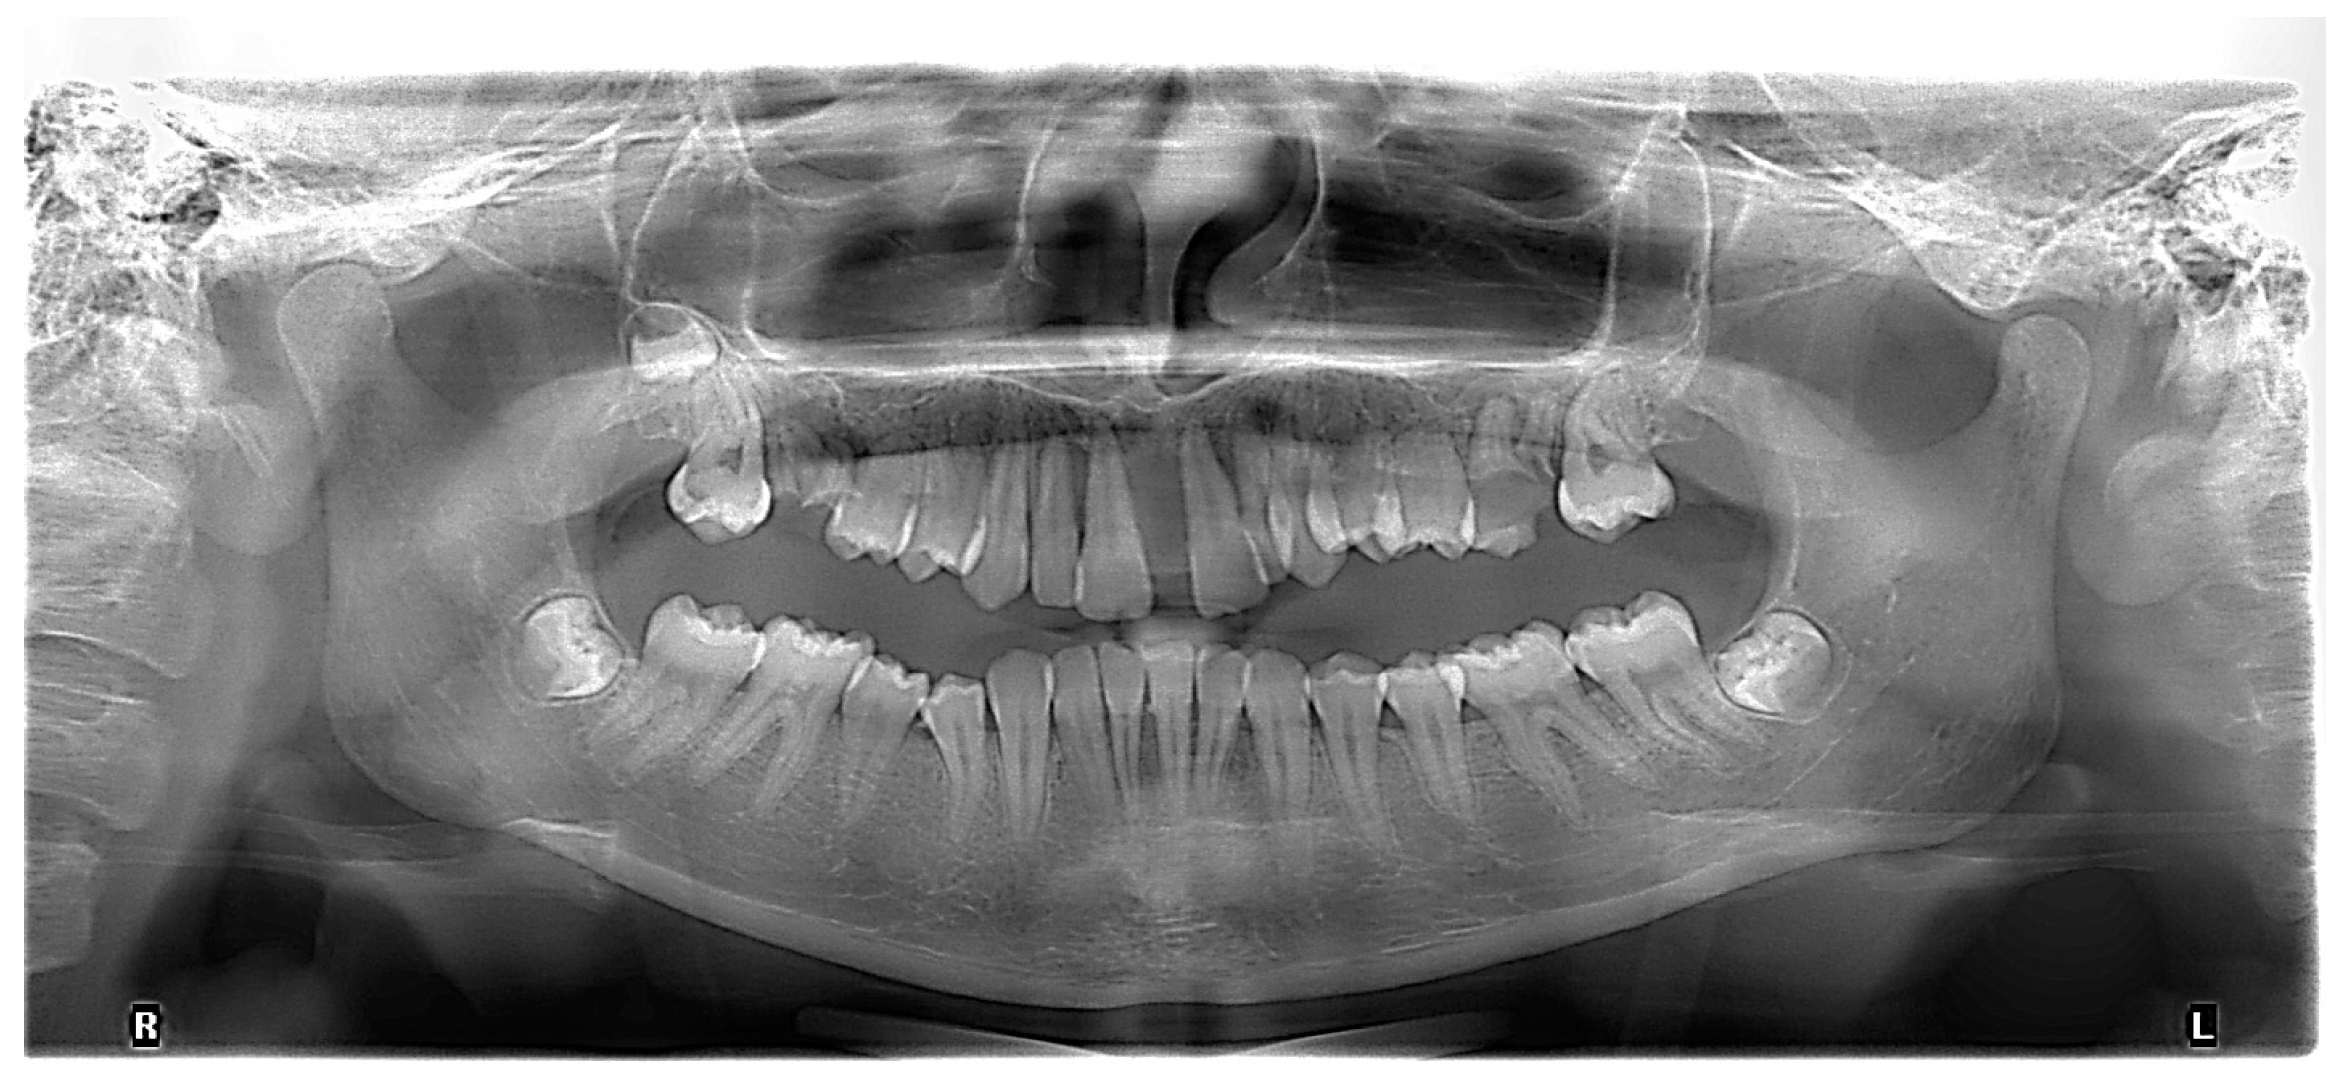

Figure 3.

Initial panoramic radiograph.

The initial radiography showed severe bone loss on the maxillary anterior tooth (Figure 3). In addition to the periodontal aspects, dental malposition of the maxillary and mandibular central and lateral incisors, deep bite malocclusion, deep hard palate, and advanced carious lesion in both maxillary first molars were observed. It was also not possible to specify whether the bone resorption in the anterior area was related to the trauma, considering that after the trauma, the patient did not request dental treatment.